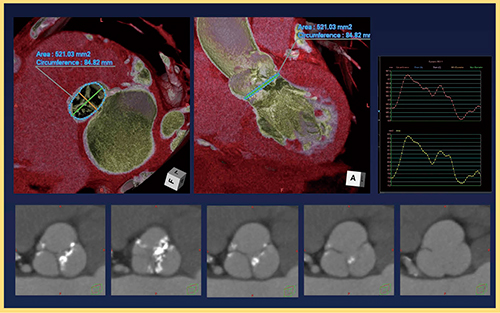

1.小児領域

小児循環器領域において,面検出器CTは圧倒的に有用である。面検出器CTでは上端・下端が等時相の画像を高速に得ることが可能であるため,呼吸停止ができなくとも安定した画像が得られ,鎮静剤が不要となる。特に血管奇形など,上下方向の関係を把握する必要がある検査では非常に有用で,面検出器CTは必要不可欠である(図1)。

図1 小児領域のVolume Scan